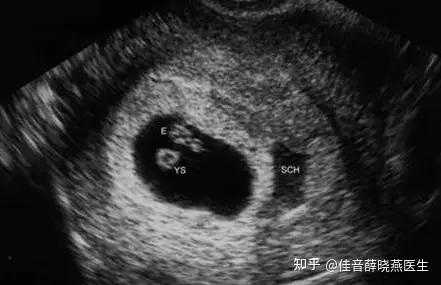

B超检查的“超”,指的是超声波,人耳听不到的高频声波,医用超声波检查的工作原理,即将超声波发射到人体内,当它遇到界面时会反射及折射,并且在人体组织中可能被吸收而衰减,探头发射的超声波输出功率很小并且超声波的检查剂量也没有累加效应,所以如果临床医生有需要,即使多检查几次对胎儿和母体也不会造成伤害。孕妈妈们千万不要误以为超声和X线或CT一样,是依靠放射线进行成像的,它们是两种截然不同的检查方法,超声也是其他检查所不能替代的。

医学影像科医生介绍,到目前为止,没有任何证据能够证明超声对胎儿有辐射,也没有因超声检查而导致胚胎死亡或胎儿畸形的报告;相反,关于超声检查诊断出各种畸形和发育异常的报告却越来越多,所以,为了宝宝们和妈妈们的安全,给超声检查一份信任,我们还您十分责任。